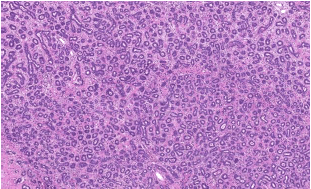

Mulher, 20 anos, com nódulo palpável na mama esquerda. Assinale a alternativa que apresenta o diagnóstico que a figura abaixo ilustra.